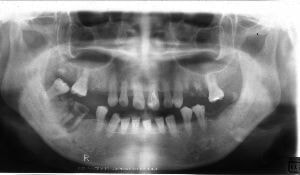

治療例1 (インプラント補綴+矯正)